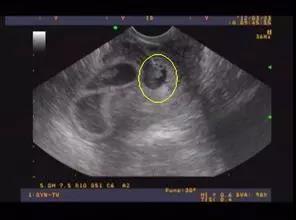

24周是孕期的一个重要阶段,此时胎儿已经发育到一定程度,器官结构逐渐完善,系统B超可以更全面地评估胎儿的生长发育情况。通过系统B超,医生可以观察胎儿的各个器官、四肢、头部等部位,及时发现潜在的问题。

系统B超的检查内容主要包括以下几个方面: